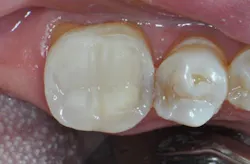

Pulpdent Corporation announces a new addition to its flagship Activa line of dental restorative materials: Activa BioActive Bulk Flow. The new product raises the standard of care for bulk-fill procedures by supporting the natural remineralization process,1 providing defense against secondary caries,2 and offering superior esthetics through its ShadeFusion universal shade matching technology. Activa BioActive Bulk Flow gives dentists a new tool to perform Class II restorations, one of the most common treatments in dentistry.

Traditional limitations were squarely in mind with the development of Activa BioActive Bulk Flow, which addresses these shortcomings. It self-levels easily, flows naturally, and exhibits elevated chroma and translucency matching. Independent testing demonstrates Activa BioActive Bulk Flow provides superior protection against microleakage,3 volume wear,4 and shrinkage stress,5 all at thresholds that meet or exceed existing standards for top-tier restorative materials.